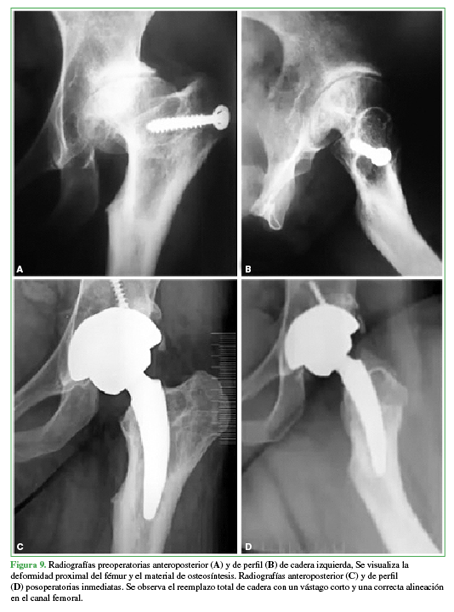

Las deformidades femorales proximales son generalmente una consecuencia de enfermedades del desarrollo de la cadera durante la infancia, fracasos de osteotomías previas o secuelas de fracturas (Figura 9).

Las anomalías anatómicas del fémur proximal pueden ser un desafío para lograr una reconstrucción biomecánica adecuada. Dificultades técnicas, tiempo quirúrgico y abordaje prolongado, altas tasas de complicaciones, necesidad de más de una cirugía y malos resultados funcionales se han relacionado con este procedimiento quirúrgico.

Se analizaron prospectivamente 31 pacientes (35 caderas) con deformidades femorales proximales tratados con ATC primaria no cementada utilizando un vástago corto con fijación cervicometafisaria (MiniHipTM). Hubo 19 pacientes masculinos (23 caderas) y 12 femeninos (12 caderas), con un IMC medio de 26,7 ± 4,1 kg/m2. Doce casos (38,7%) tenían un antecedente de procedimiento quirúrgico, y seis de ellos fueron osteotomías infantiles fallidas. La edad media de la serie fue de 44 ± 12 años, el seguimiento medio fue de 81 ± 27 meses y no hubo pérdidas de seguimiento de ningún paciente. Las deformidades femorales proximales se categorizaron de acuerdo con una clasificación de Berry modificada.48 El ángulo cervicodiafisario femoral preoperatorio varió entre 90° y 157°. La discrepancia preoperatoria promedio en la longitud de los miembros inferiores fue de -16,3 mm (rango de -50 a 2). En comparación con la cadera contralateral, la lateralización femoral preoperatoria fue de -7,6 mm en promedio (rango de -28 a 8).